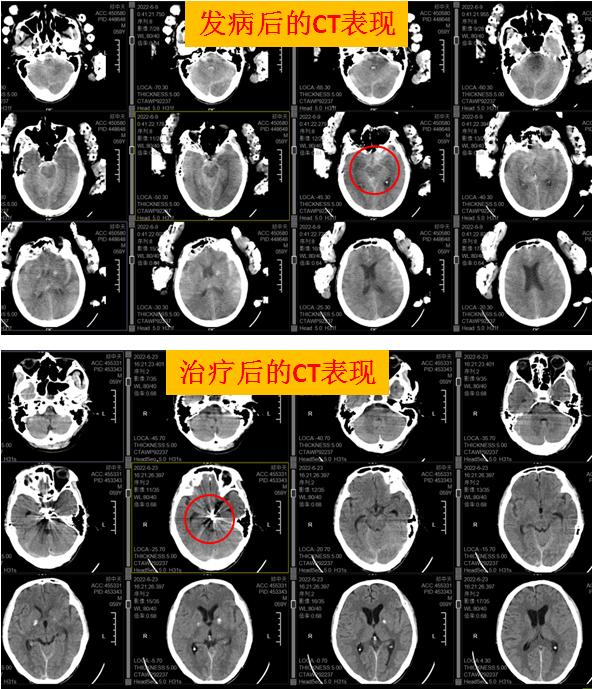

患者郑某在家中突发昏迷不醒,由120救护车送入我院救治,我院神经外科立即启动卒中绿色通道,行头颅CT和DSA脑血管造影提示:脑内动脉瘤破裂伴蛛网膜下腔出血。因脑内动脉瘤随时都有可能再破裂,引起脑出血,此时情况十分危险!在征得患者家属同意后,神经外科团队为郑某实施脑内动脉瘤介入治疗,用弹簧圈栓塞动脉瘤,经过3个小时的努力,弹簧圈被顺利放入动脉瘤腔处,将动脉瘤与正常血管完全隔离,达到防止再出血的效果,手术成功!

这次对患者实施的DSA全脑血管造影+脑内动脉瘤弹簧圈介入栓塞术是神经介入治疗的一种方式,手术利用现代影像技术把弹簧圈填充到动脉瘤腔里,让血液无法进入,达到避免脑出血的目的。该介入治疗具有创伤小,恢复快,痛苦小等优点,是目前介入治疗脑动脉瘤的首选方法。